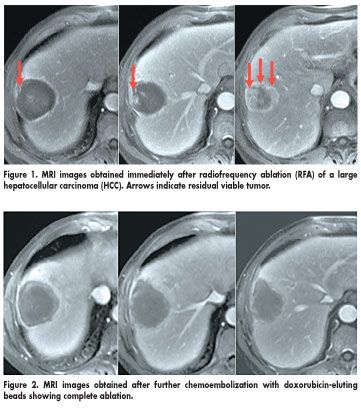

Study participants were 20 patients who had uninodular HCCs larger than 3 cm in diameter and unequivocal evidence of residual viable tumor on CT or MRI scans obtained immediately after RFA. Within 24 hours, the patients underwent Precision TACE (transarterial chemoembolization) with drug-eluting beads (DC Bead, Biocompatibles International, Farnham, UK) loaded with doxorubicin. (DC Beads are investigational in the United States.)

According to EASL (European Association for the Study of the Liver) criteria, 14 of 20 patients (70%) had an objective complete response, and 6 patients (30%) had an objective partial response with the combined treatment.